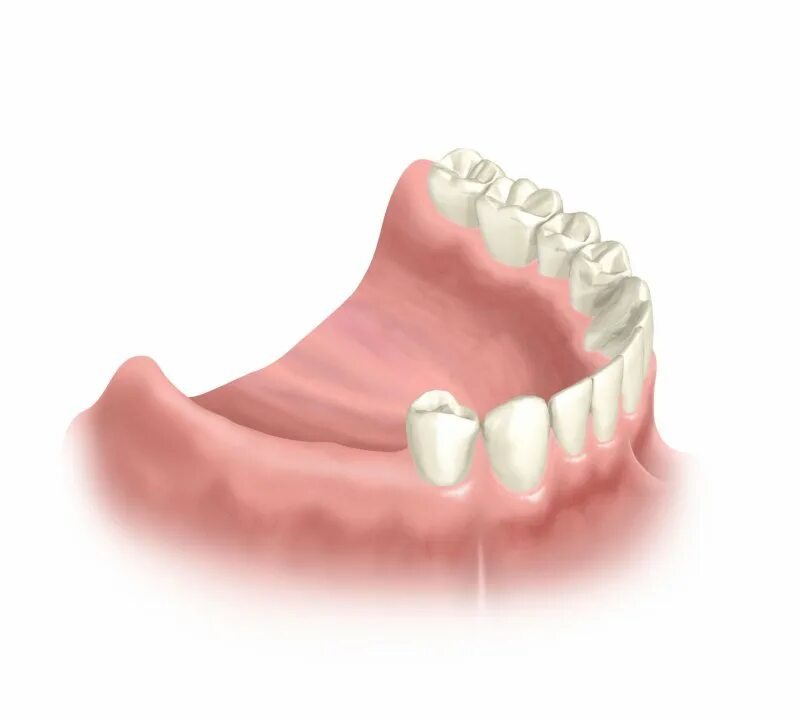

Поставить 4 зуба